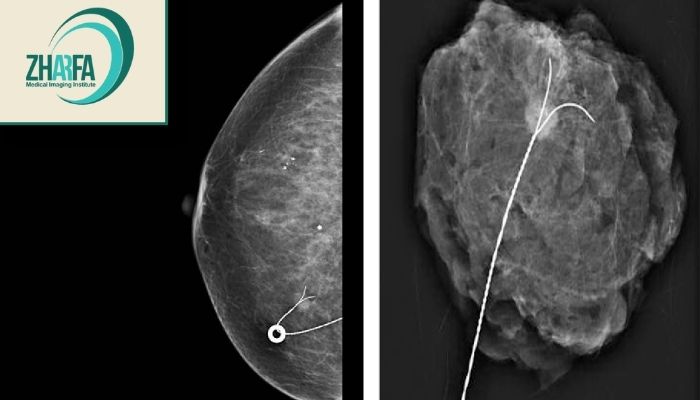

معمولاً بین ۱۰ تا ۲۰ دقیقه زمان میبرد بسته به نوع ضایعه و ابزار تصویربرداری مورد استفاده.